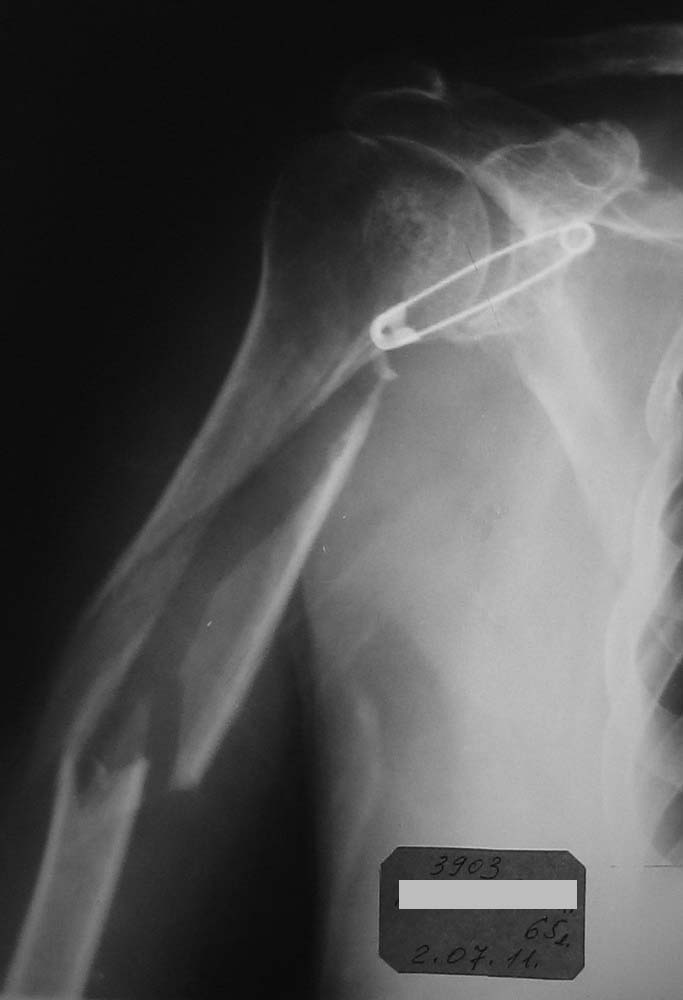

Хотелось бы увидеть снимки и руку на сегодняшний день. Причина проблем- неадекватный и нестабильный остеосинтез, осложнившийся остеомиелитом и несращением, и повторная травма тут ни при чем.

Оба предложенных варианта подходят, но важно увидеть длину оставшегося дистального отломка, состояние суставов.

Последний R-снимок - со стержневым аппаратом.